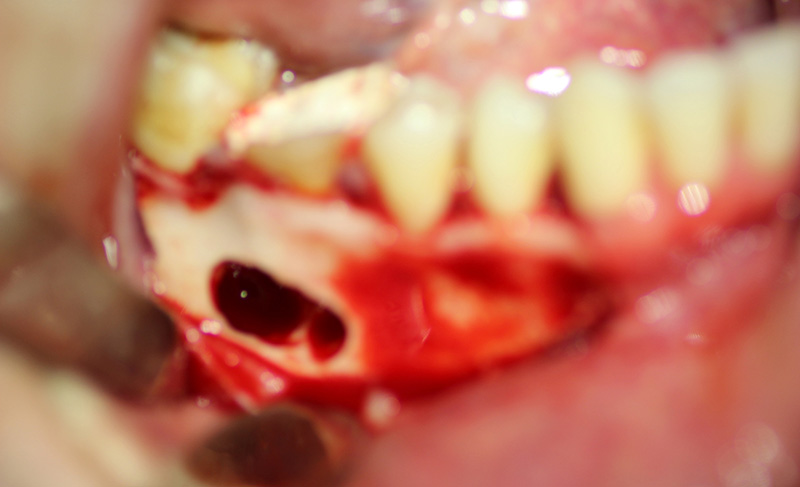

The patient underwent an operation of apicotomy (resection of the apex of the tooth root) and removed the cyst.